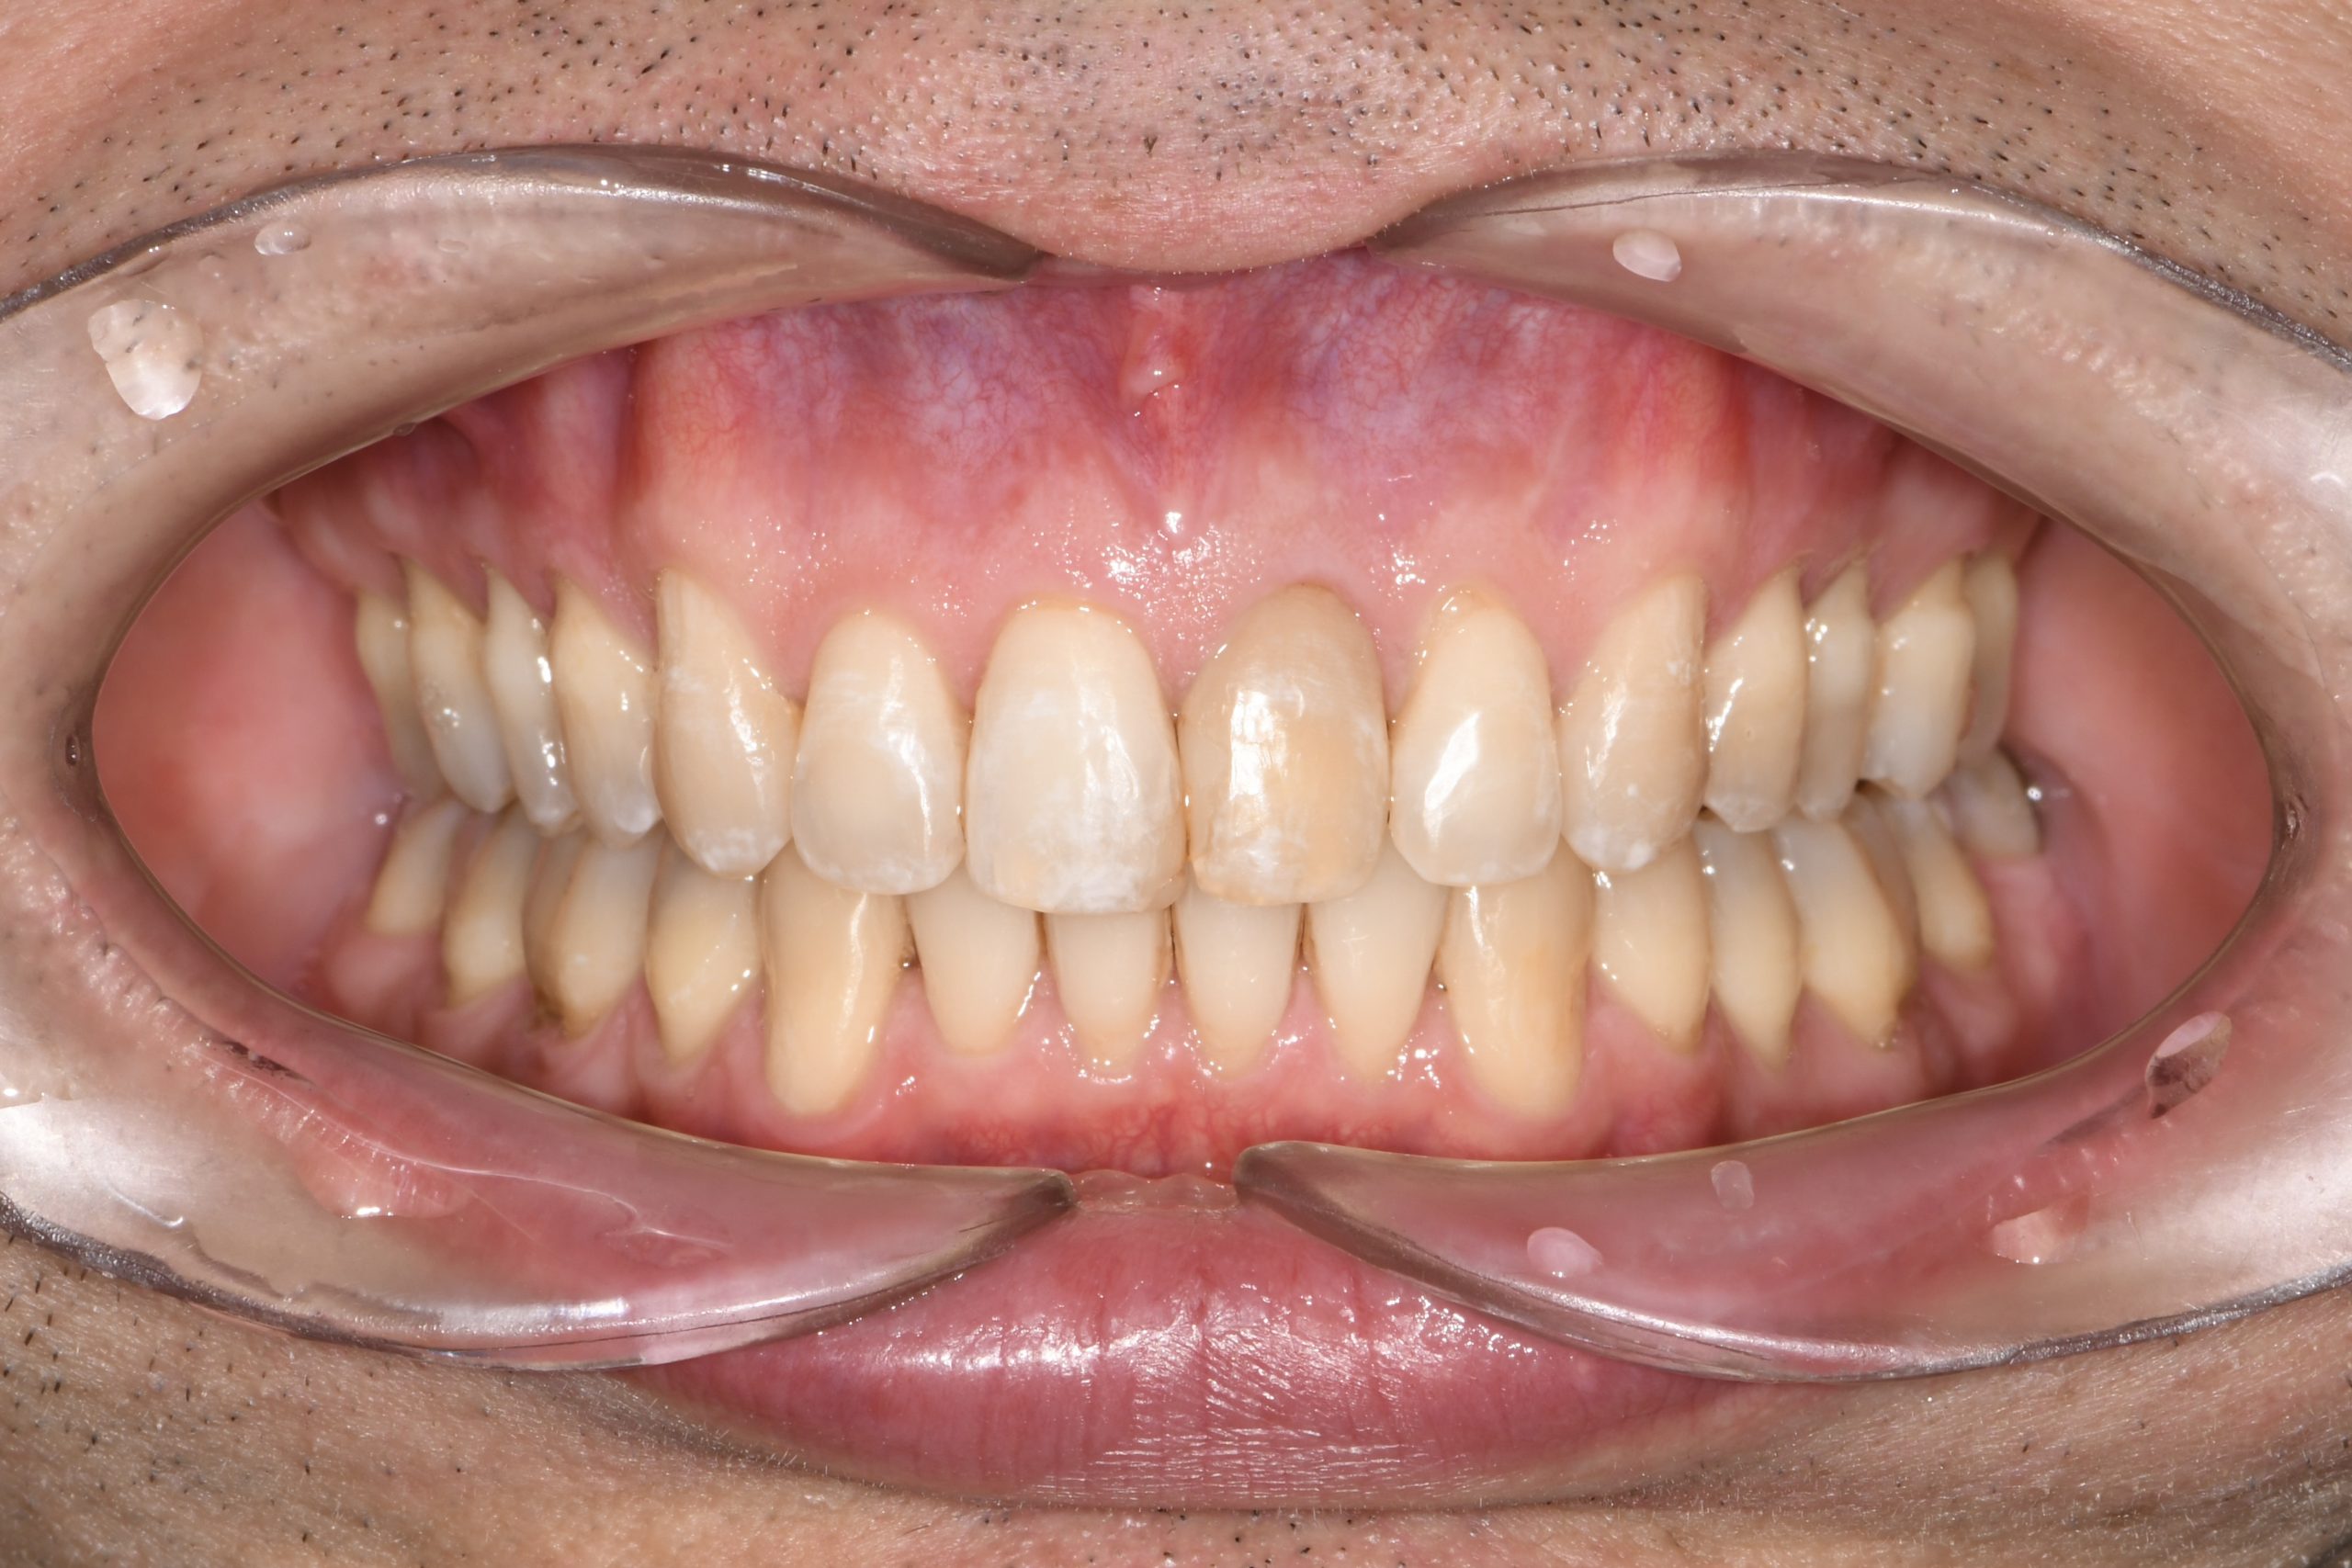

Az elmúlt évekből rengeteg szakmai referenciát tudnánk bemutatni, amelyek különböző fogszabályozási problémákat oldottak meg. Válogatva a több száz esetből, ezen az oldalon olyan képeket, információkat igyekeztünk bemutatni, amelyeknek a segítségével a jövőbeni pácienseinknek azt tudjuk üzenni: A Te fogsorod is lehet gyönyörű!

(Képeket a Pácienseink külön írásos beleegyezésével mutatjuk be!)